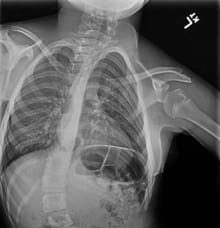

Paige’s spine after surgery with rods and screws inserted using FIREFLY® Technology.

When Dr. Hardesty placed the guides on the patient's spine during surgery, she could see precisely where to place rods and screws – despite the significant twists and turns of her young patient's spine.

“Using FIREFLY® decreases the risk of spinal cord, nerve and tissue damage. Knowing you're in the right place the first time you attempt to place a pedicle screw is safer for the patient’s anatomy. It also reduces the patient’s exposure to radiation and anesthesia, further enhancing patient safety,” Dr. Hardesty says.